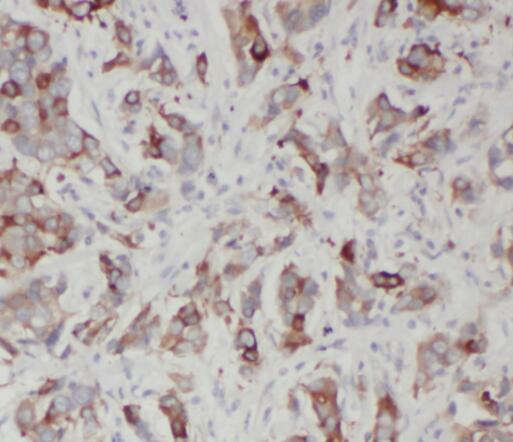

Immunohistochemistry of paraffin-embedded human breast cancer tissue slide using FNab08209(SQLE Antibody) at dilution of 1:50 IP Result of anti-SQLE (IP:FNab08209, 3ug; Detection:FNab08209 1:300) with A549 cells lysate 920ug.